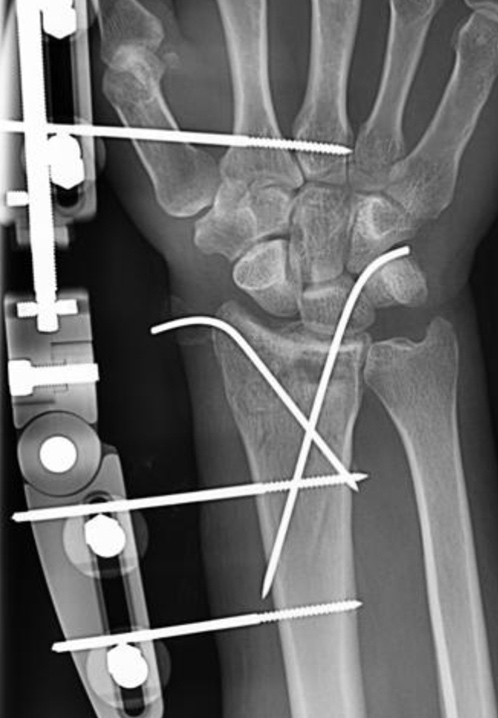

Dynamic Distal Radius

External Fixators

Concept

Distal radius fractures represent the most prevalent fracture type encountered in emergency settings. External fixation stands out as one of the optimal treatment modalities for managing distal radius fractures, particularly beneficial in cases involving articular or metaphyseal comminution.

Adjustment of the articular components of the external fixator is conducted in accordance with radiological parameters of the unaffected side.